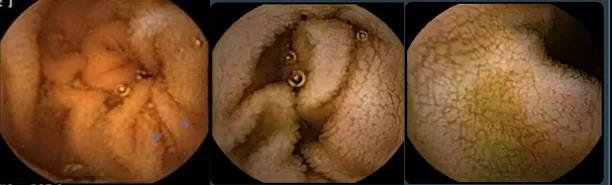

胃镜:十二指肠球部及十二指肠降部:皱襞平坦、变小或消失;圆齿状皱襞,裂沟;绒毛萎缩

肠镜:可见回肠末段绒毛扁平萎缩,结肠黏膜正常

胃镜病理:十二指肠绒毛萎缩、上皮内淋巴细胞明显增多

肠镜病理:回肠末端:绒毛明显萎缩,上皮内淋巴细胞增多,潘氏细胞和杯状细胞没有减少;免疫缺陷相关和淋巴瘤相关的免疫组化阴性。